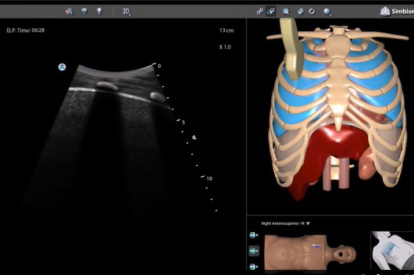

Ultrasound Mentor accelerates the development of basic to advanced technical and cognitive skills, by providing not only the probe manipulation training, but also a didactic environment enabling structured, self-guided learning including step-by-step instructions and educational aids such as 3D anatomical map and probe positioning assistant, all backed up with our progress monitoring tool MentorLearn.

- Step-by-step tasks provide a self-learning opportunity for sonography skills and scanning protocols

- Advanced diagnostic tools, including Color Doppler, CW, PW, M-mode, and measurements

Bedside Echocardiography Module

Advanced Echo Module